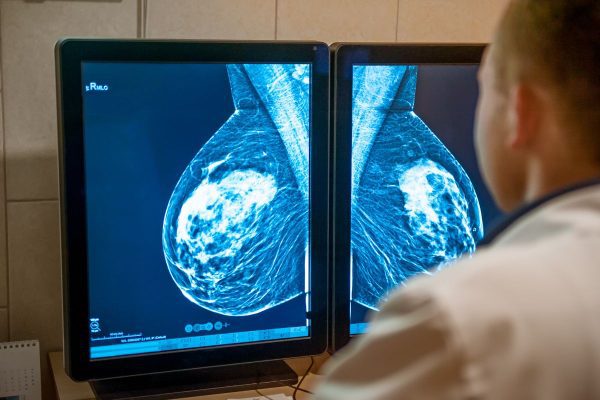

Un estudio revela que la IA puede identificar riesgos de cáncer de mama hasta seis años antes del diagnóstico clínico, abriendo nuevas posibilidades para tratamientos preventivos personalizados. En un avance significativo en la lucha contra el cáncer de mama, investigadores han descubierto que la inteligencia artificial (IA) puede detectar señales de la enfermedad en mamografías…